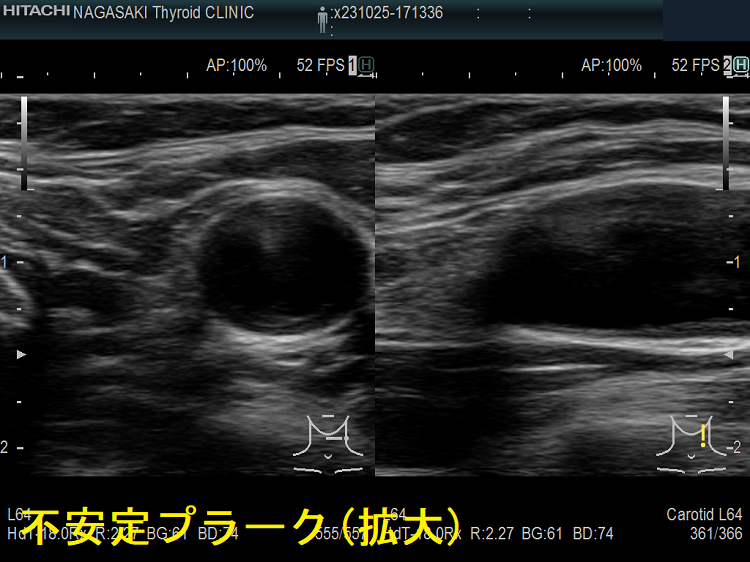

動脈硬化が進んだ血管にはプラーク(コレステロールエステルを大量に含んだ脂質の塊)(矢印)ができて、血管内が狭くなります。血管エコーでプラークを探す。動脈硬化した血管は硬くもろいため、大動脈では血圧に負けて大動脈瘤になることがあります(急性大動脈解離・大動脈瘤)。

(↓)デジタルハイビジョン超音波装置で見たプラーク。